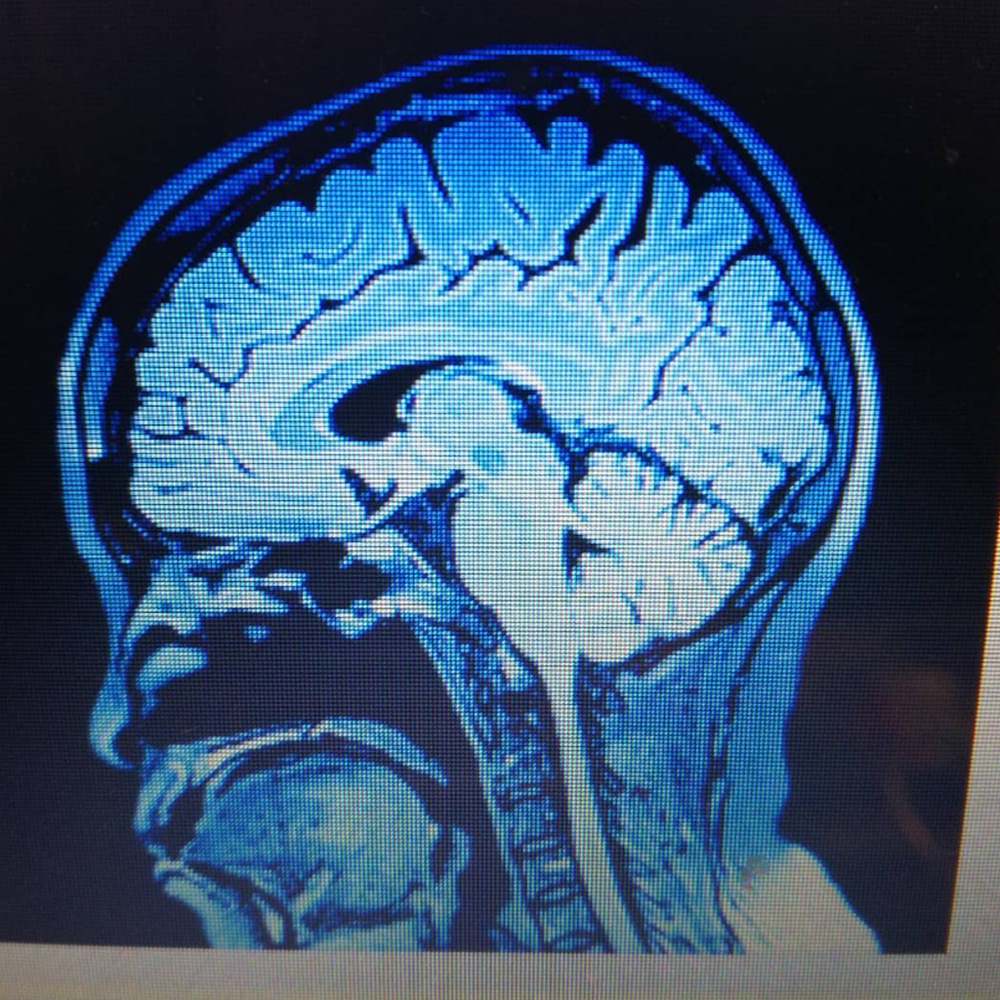

Omurilik Yenilenmesi

Düşme ve kaza sonucu beyin ve omurilikte oluşan darbeye bağlı sorunlar, doktorları çok zorlayan , hastanın hayatını da tamamen değiştiren çok ağır bir klinik durum...